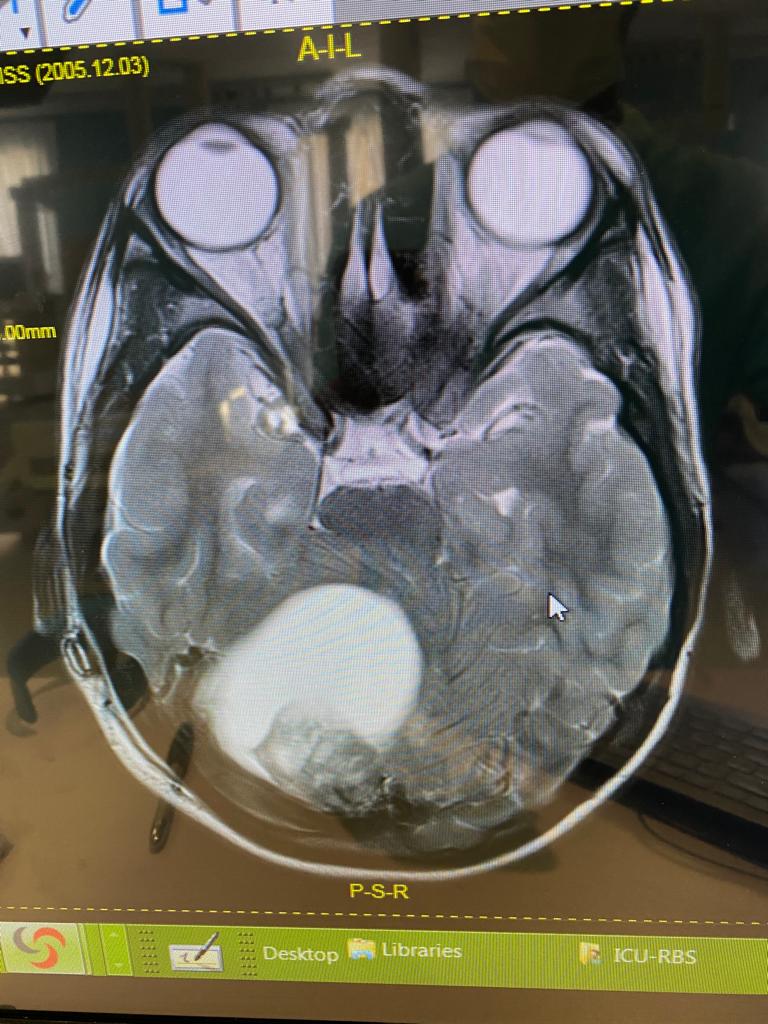

The work we do

S.T.D Neurosurgical Health Centre